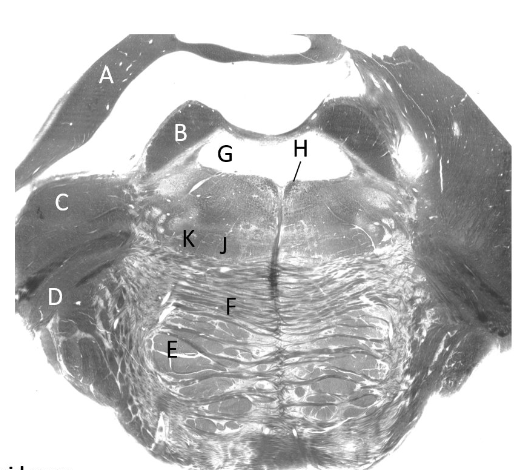

at what level is this?

mid-medulla

what is a?

inferior cerebellar peduncle

what is b?

medial lemniscus

what is c?

pyramidal tract

what is d?

inferior olivary nucleus (m)

what is e?

hypoglossal nerve fibres

what is f?

inferior vestibular nucleus

what is g?

medial vestibular nucleus

what is h?

dorsal nucleus of vagus

what is J?

median longitudinal fasciculus

what is k?

hypoglossal nucleus

what is L?

olivocerebellar fibres

what is m?

olive

what is n?

4th ventricle (m)

what is o?

solitary tract